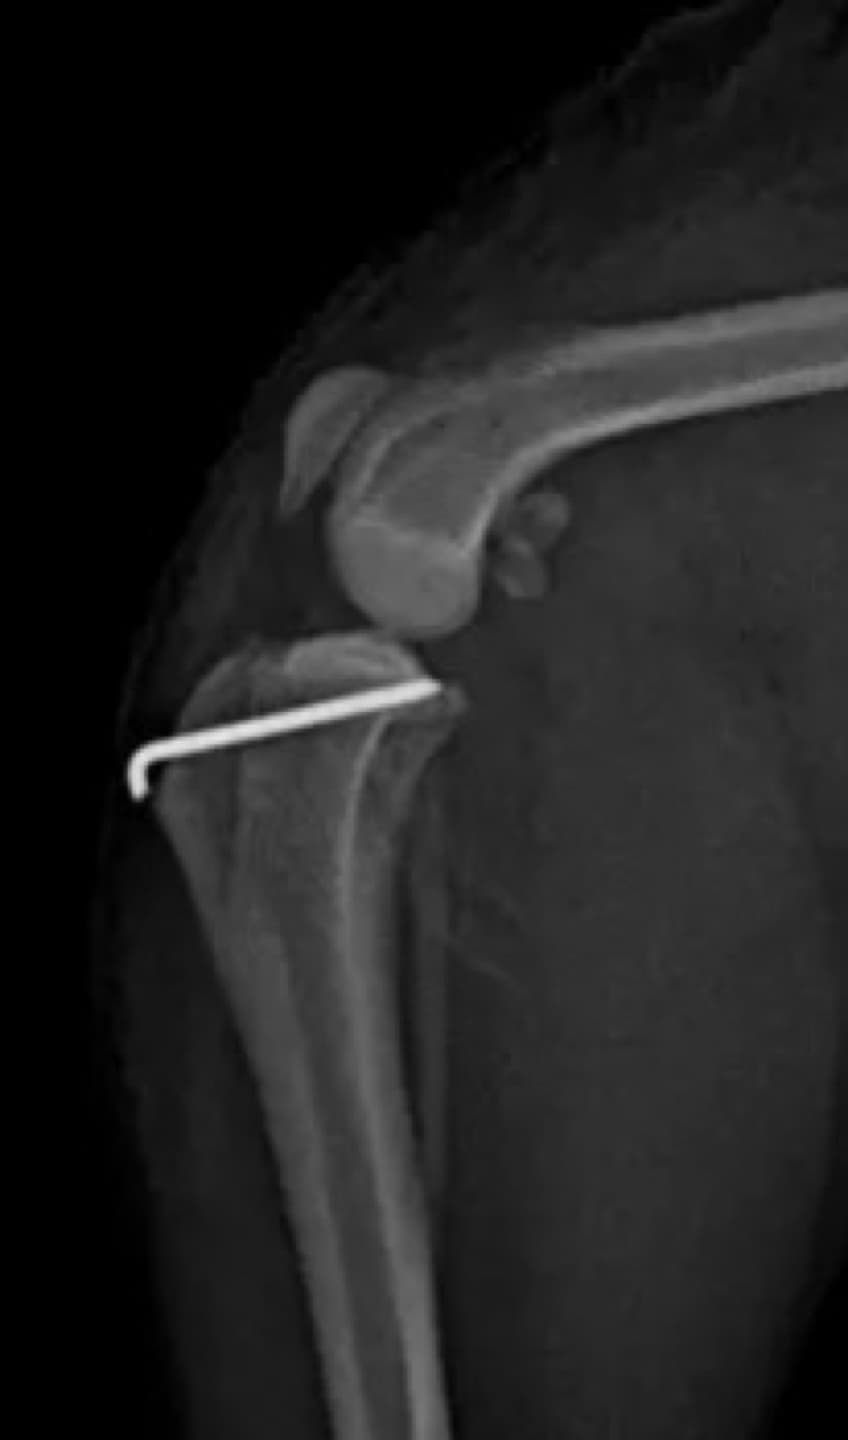

정형외과 전공의 수의사가 직접 수술합니다.

02C-arm을 통해서 좀 더 섬세한 정형외과 수술을 진행하고, 본원에서는 외과적 침습을 최소화 하는 중재적 시술 (기관 협착, 동맥관개존증(PDA), SUB 등)을 진행하고 있습니다.

11유명한 Stryker사 장비. 골절 수술, 절골등 다양한 정형/신경외과 수술시 사용

12정교한 정형외과 도구를 사용하여 신속 정확한 정형외과 수술이 가능

13수술 중 골절 상태 혹은 이식물 적용 후 상태 등 육안으로 명확히 확인하기 힘든 상태를 X-ray 확인하여 정확한 수술 결과를 만들어 내는 것이 가능